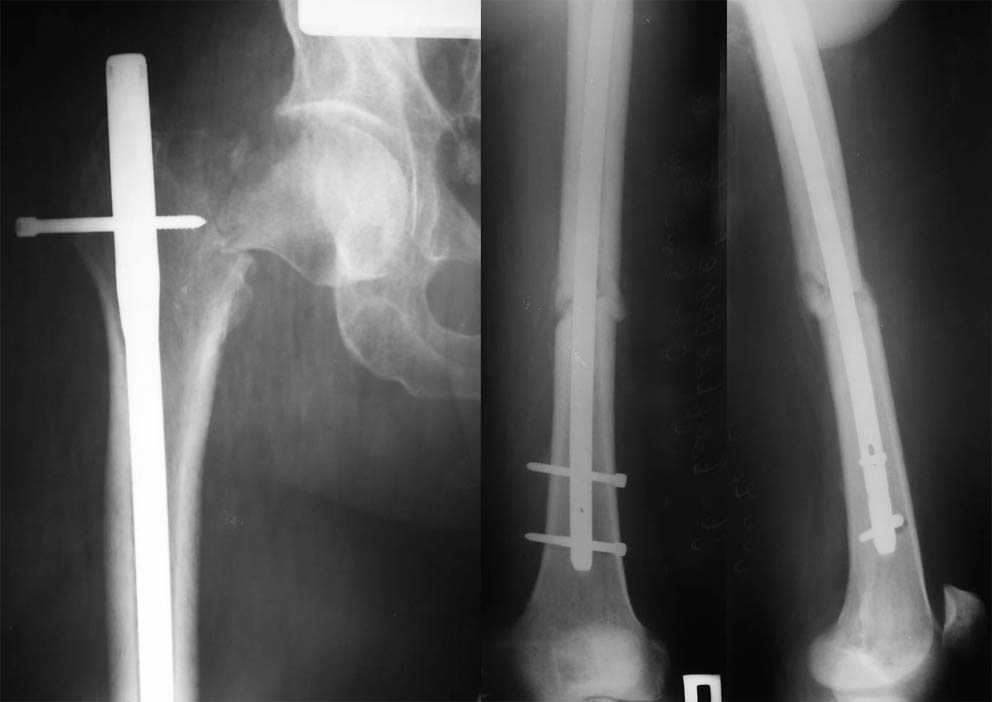

Больной Н., 38 лет, получил травму в результате ДТП. Был доставлен в

одну из больниц города Самары. Выполнен антероградный остеосинтез

диафиза правого бедра штифтом с блокированием (ChM). При выполнении

контрольной рентгенографии был обнаружен перелом шейки бедра,

пропущенный на этапе первичного обследования. Больному было разрешено

передвигаться на костылях, без опоры на правую ногу. По прошествии 4х

месяцев больной обратился к нам в клинику. Хотелось бы услышать Ваше

мнение по поводу дальней тактики лечения.